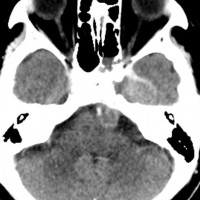

骨軟骨腫が若い時からあって壮年になってから悪性化した軟骨肉腫です。20代のときに右外転神経麻痺が生じて20年以上そのまま経過しました。左のCTでは頭蓋骨の真ん中の斜台というところに異常な骨があって,良性の骨軟骨腫のように見えます。でも右側のMRIでは脳幹部に深く食い込む柔らかい腫瘍の部分が写っていてこれは軟骨肉腫を疑う像です。手術摘出と術後の放射線治療をしました。